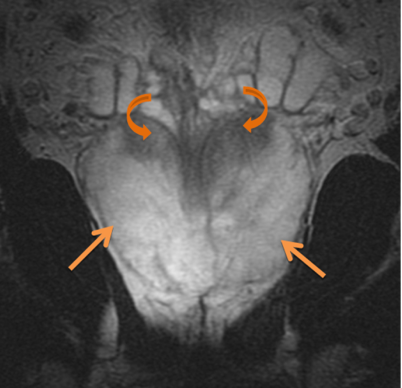

Additional imaging studies include an MRI of the prostate, generally with endorectal coil. If the PSA is > 20 then a bone scan is reasonable. A transrectal ultrasound is an intrinsic part of the biopsy in recent years. Peripheral zone cancers can be seen on the ulltrasound with hyper-echoic lesions in 69% of the cases. CT of the pelvis and prostate are used in radiotherapy treatment planning. Discrepancies between CT and MRI on fused images may exist (Roach):

Poor correlation of the prostate apex was found between these modalities. The retrograde urethrogram was tested to insure that the urethrogram itself did not displace the prostate by pre- and post-urethrogram MRI studies which demonstrated no artifactual displacement as a result of the urethrogram. Roach examined 10 patients and noted that the prostate volume was 32% larger on non-contrast CT than when determined by MRI. The regions of most non-agreement were posterior-inferior (neurvascular bundles) and posterior extent of the gland. The CT volume for prostate and seminal vesicles was 40% larger on the average than the MR with the CT variant 8 mm larger at the base of the SV and 6 mm larger at the apex. This was corrected for and persistent with interobserver variation.

There is significant variation of contours and techniques. The apex and base are regions most susceptable to variation. 3D perspectives help signficantly reduce this variation using transverse, sagital and coronal projections to determine the true extent of the prostate. More recently contouring atlases have been developed by the RTOG with grant assistance from the NCI and are available here. The following images are obtained from the RTOG contour atlases as an excerpt demonstrating areas of potential uncertainty.